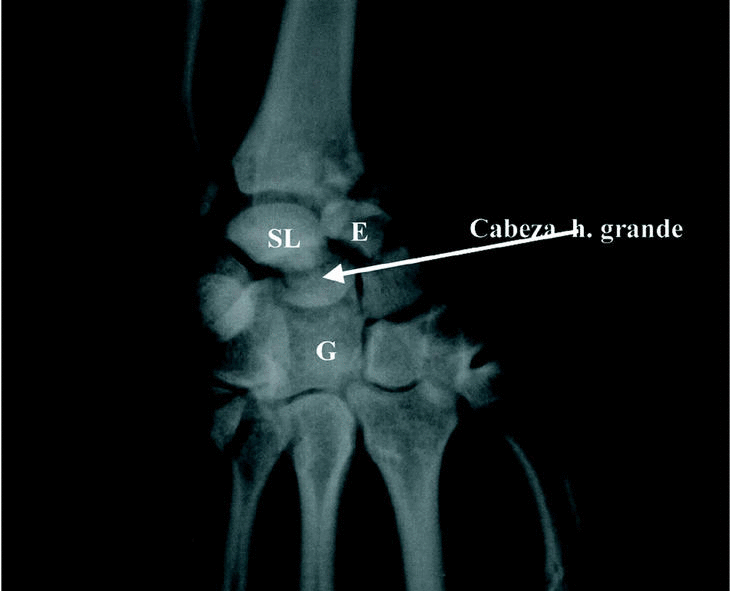

Paciente de 22 años que sufrió accidente de motocicleta, presentando fractura de cabeza radial izquierda y fractura-luxación transescafocapitolunar derecha. En la radiografía inicial (Fig. 1), se observaba la luxación perilunar con una fractura desplazada del cuerpo del escafoides y del hueso grande, con rotación de 180° del fragmento proximal de este último. Se procedió a la reducción abierta de urgencia, por vía palmar, reduciendo y sintetizando el escafoides y el hueso grande, en este orden, mediante agujas de Kirschner que los fijaban a radio y semilunar. Las agujas se mantuvieron 5 semanas y el yeso antebraquial 60 días en total, iniciando posteriormente rehabilitación. Tras 2 años de evolución presentaba en la muñeca un arco de movilidad indoloro de 50° de estensión y 60° de flexión, sin limitaciones para su actividad diaria, por otro lado poco exigente. En la radiografía se observó osteoporosis difusa del carpo, con esclerosis del polo proximal del escafoides y de la cabeza del hueso grande, por la necrosis avascular de los mismos, es asintomática.

Figura 1. Caso 1: Radiografía preoperatoria. SL = semilunar, G = hueso grande, E = escafoides.